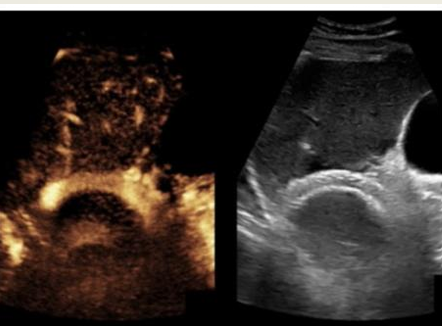

what lesion is seen on this CEU?

HCC